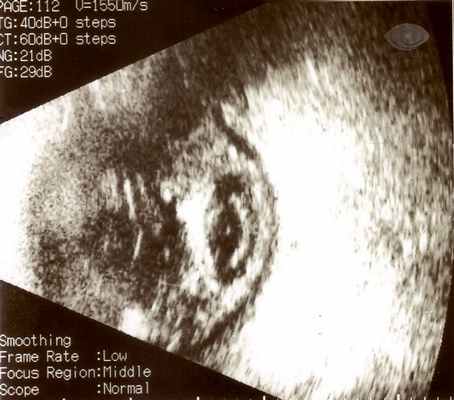

Биомикроскопия. Гипопион.

- Биомикроскопия. Проведение биомикроскопии выявляет смешанную инъекцию глазного яблока, наличие преципитатов на поверхности роговицы, гипопиона, гиперемию и инфильтрацию радужки, образование задних синехий